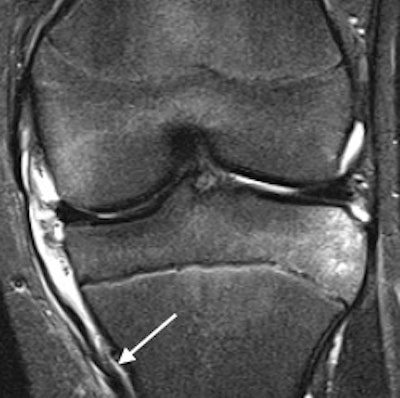

Distal rupture of the medial collateral ligament (arrow) on coronal short-tau inversion recovery of a 15-year-old boy. All images courtesy of Drs. Jacob Jaremko and Zachary Guenther.Along with colleagues from Ghent University Hospital in Belgium and Mater Misericordiae University Hospital in Dublin, he has shared his experiences of imaging of ACL tears in an article in Insights into Imaging, posted online on 9 May. The authors are concerned that insufficient attention is given to children and adolescent injuries.

In these cases, radiologists must be aware of tibial spine avulsion instead of ACL rupture, a thin but intact ACL, poor visualization of posterolateral corner structures, and differentiation between incompletely closed physis and impaction fracture. The posterior lateral meniscus is particularly complex and should be studied in three regions (posterolateral corner, meniscofemoral ligament attachment, and bony attachment), and if an ACL tear is detected, the associated findings described here should be specifically sought and, conversely, observing one of these findings should increase the suspicion for an ACL tear, they stated.

- Axial MR sequences are more sensitive/specific than coronal for diagnosis of medial collateral ligament injury.